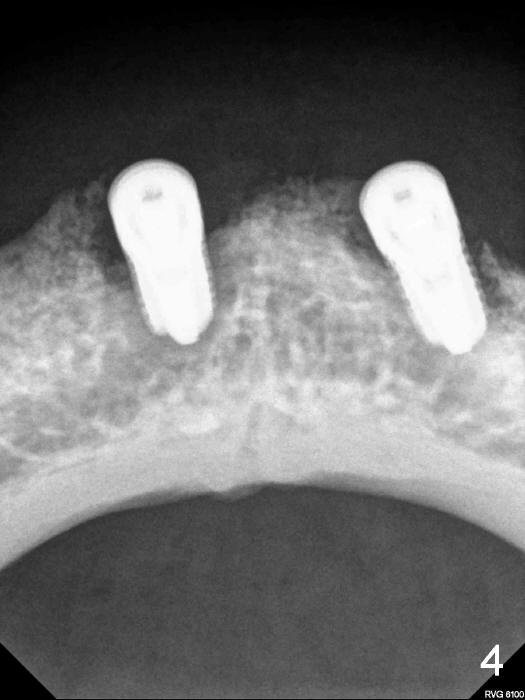

Here is another case: female, 68yrs, two implants supported overdenture, panorex was preop (Fig.1), pa with two implants was taken one week after implant insertion (Fig.2), another pa with some shadow was taken one month after surgery (Fig.3). Now presented fistula on the alveolar ridge. I have not idea what is going on? Do you have any idea/what causes it?  It happened couple cases already.  I handled these kinds of cases: take out implants, wait for healing and place implants again.